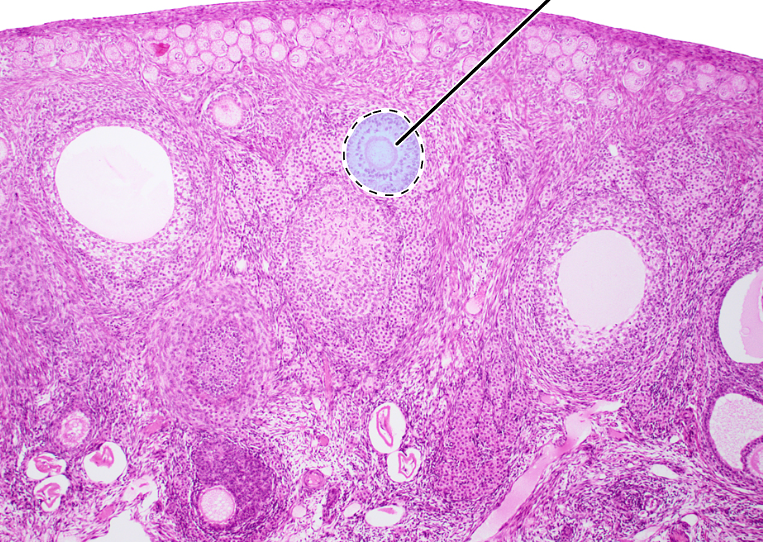

ovary (sagittal section)

primordial follicles

antrum

corona radiata

oocyte

mature tertiary follicle